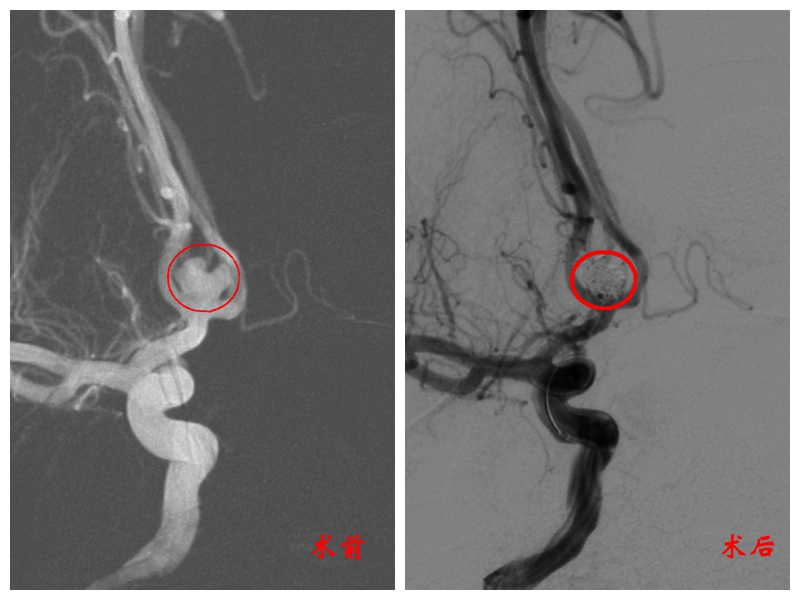

“患者动脉瘤位于大脑前交通区,位置较远且形状不规则,她的大脑血管也比常人更弯曲,这些对我们来说,都是挑战。”曾怀文解释,“在DSA下,我们可以看到患者动脉瘤不是规则的圆形,有两个子瘤,要全部填满填实就比较费时费力。”

尤其是瘤径较宽,在堵塞瘤体的同时,还要确保弹簧圈不会掉落,影响血液流通。为此,在成功栓塞致密后,团队又通过导管,植入两枚支架,“撑开”血管,避免主干梗塞。

一边要堵,一边要通,神经外科团队步步谨慎,凭借精妙技艺解决了一个又一个棘手问题。

历经四个多小时,这场高难度手术才大功告成。